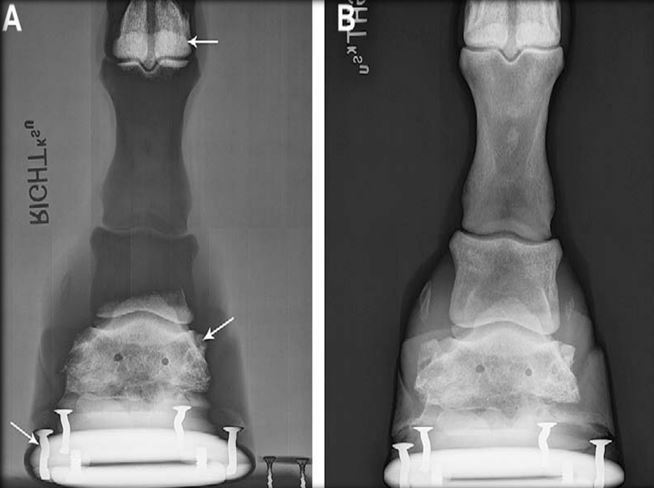

6

Q

Artifact? Fix?

A

There are two rads in that image… one with the glove is the artifact and the one without it is normal.

Density threshold - metal object change the gray-scale to exclude your wanted anatomy .

Remove metal object